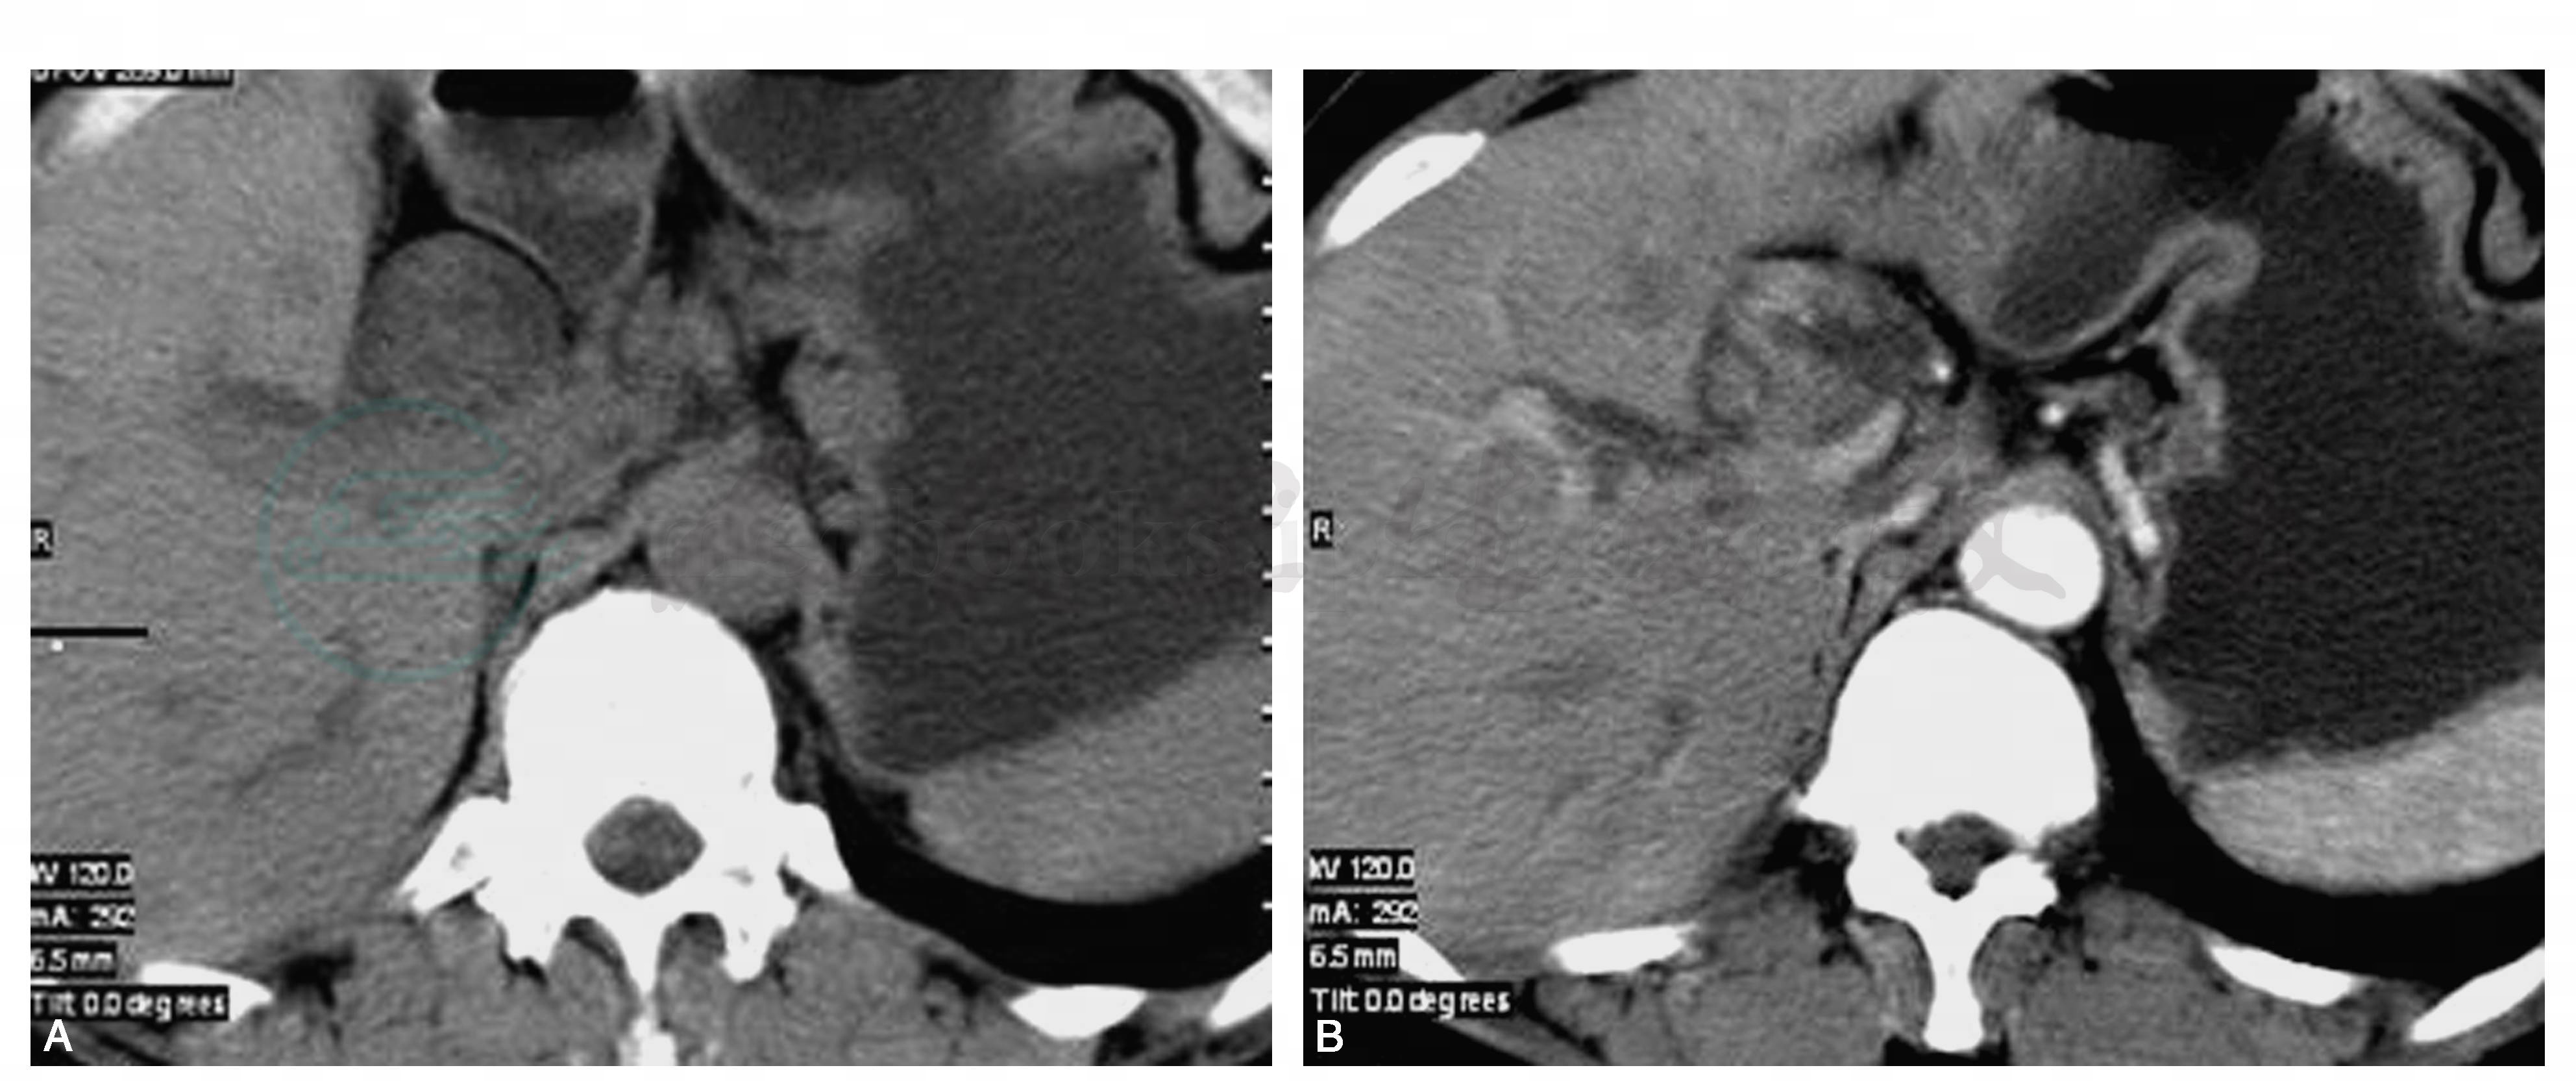

胆管腺瘤具有恶变倾向,尤其是绒毛状腺瘤,其恶变率很高,已有报告在31%~63%之间。我们在临床呈治疗2例胆总管绒毛状腺瘤,其中1例证实为恶变(图1~3)。

图1 胆管腺瘤的CT、M RCP和术中所见

CT可显示边界清楚的实质性肿块向肝内外扩张的胆管内延伸,增强扫描肿块可有不规则的强化。在MRI上可见胆管系统的扩张,病变呈树枝状、长条状生长充盈管腔内,在T1WI信号略低于或等于脾脏的信号,T2WI稍高于肝脏的信号,即高于胰腺的信号,部分病例可看到完整的胆管壁,借此往往可以与胆管癌、胰头癌相区别。增强扫描,胆管内病变呈轻度不均匀强化,胆管壁强化稍明显。病灶较小时胆总管可无明显扩张。MRCP上可以看到病变呈弥漫性生长方式充满胆管系统,但管壁尚可见,病变在MRCP和T2WI上呈中等高信号,左右肝管扩张呈高信号,病变可延伸至肝门以上(图4)。